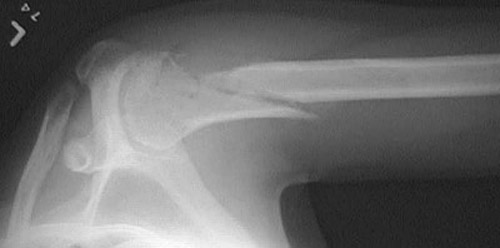

The upper humerus demonstrates a fracture that occurred as a consequence of bone destruction by a neoplasm, in this case a primary osteosarcoma. However, such "pathologic" fractures (so-called because an underlying pathologic condition causes the weakening and fracture, not trauma) may also be caused by benign tumors or tumor-like masses, metastatic disease, or by metabolic bone disease.